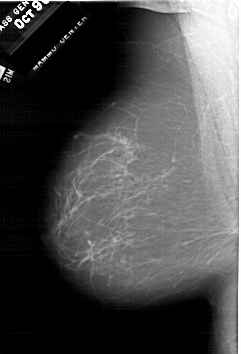

A_1950_1.RIGHT_MLO

LEFT_MLO LINES 6361 PIXELS_PER_LINE 4321 BITS_PER_PIXEL 12 RESOLUTION 43.5 NON_OVERLAY